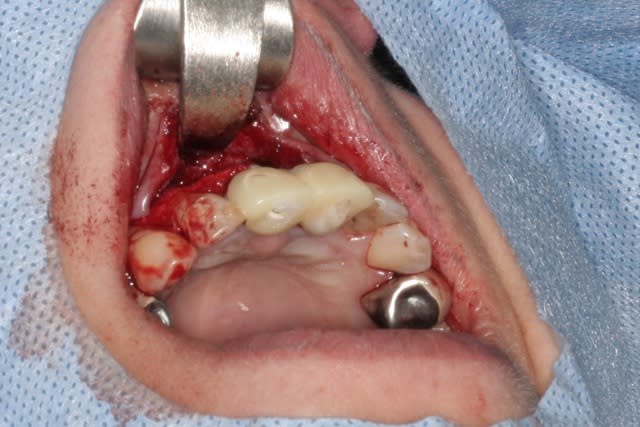

cet implant est une merveille!!!

connexion au top, pièces prothétiques aussi, facilité de pose incroyable...

tien, ce matin, extraction de 24/25, curetage méticuleux, forage, comblement du gap, pose des 2 implants qui se sont bloqués à 50Ncm au CA sur les 3 ou 4 mm apicaux, pose des vis de cicat, sutures...35min....tranquille...

désolé, la pano est un poil déformée (la patiente à du bouger...)